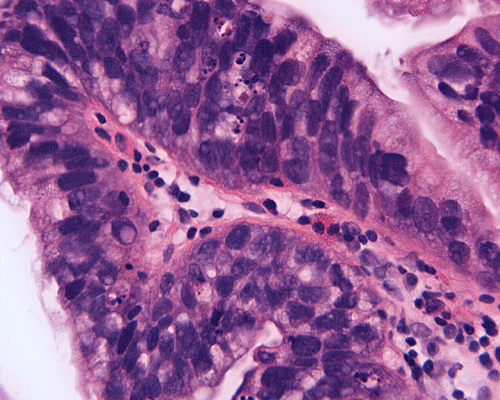

On scanning-magnification, the biopsy material consists of small nodules of stromal tissue with epithelium lined papillae (Panel A). On low-magnification (Panel B), both multilayered epithelium  and cribiform pattern (Panel C)are demonstrated. On high-magnification  (Panel D), the epithelial cells are hyperchromatic and pleomorphic. Intracytoplasmic mucin is well demonstrated by periodic acid-Schiff (PAS)- Alcian blue stain (Panel E) and mucicarmine stain (Panel F). No invasion is demontsrated.

Histologically, in situ adenocarcinoma is defined as a noninvasive glandular lesion, where the mucosa of the urinary bladder is replaced by an atypical, often pseudostratified columnar epithelium, featuring atypical cytoplasm and definitive cytologic atypia with nuclear hyperchromasia, moderate to severe nuclear pleomorphism, frequent mitosis and apoptosis 4. Necrosis is infrequently seen.

Three distinct architectural patterns have been described: papillary, cribriform and flat 2, 3, 4. Papillary architecture is the one most commonly seen, followed by cribriform pattern. Individual cases rarely show a pure pattern; rather, various combinations of the three patterns are more often seen.